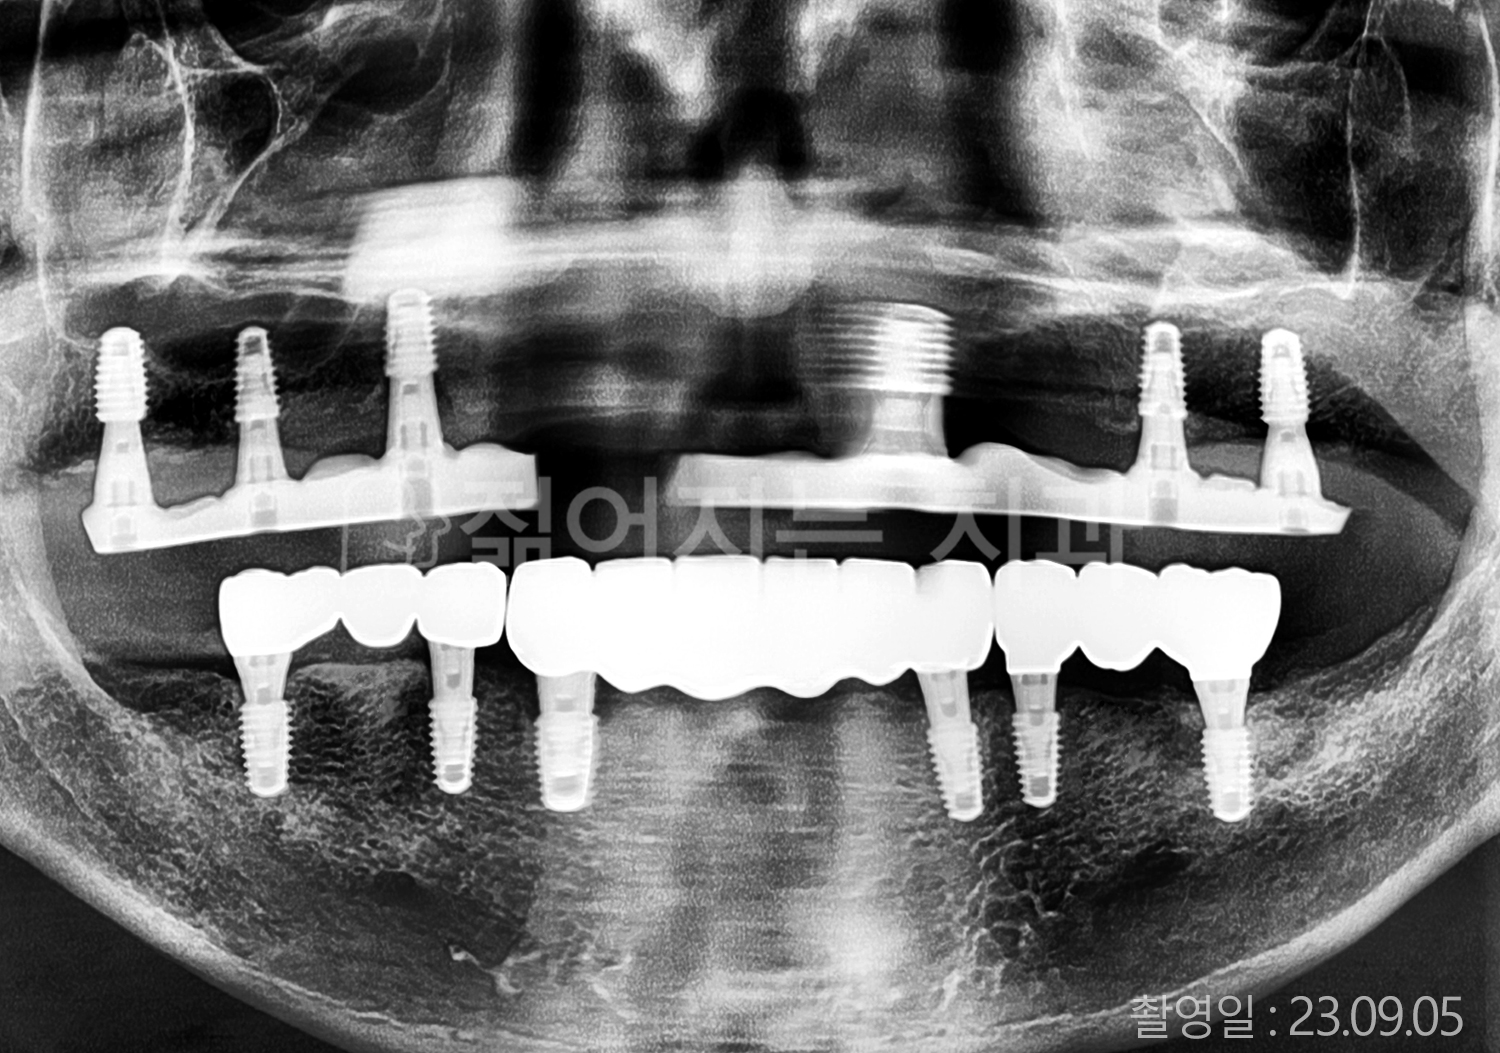

• 40대 전체치아 10개 이상 임플란트

위 사진의 저작권은 젊어지는 치과에 있습니다.

본 사진은 환자분의 동의 하에 게재 되었습니다.

* 위 사진은 동일 조건에서 촬영 되었습니다. / 모든 치료에는 부작용이 발생할 수 있습니다.